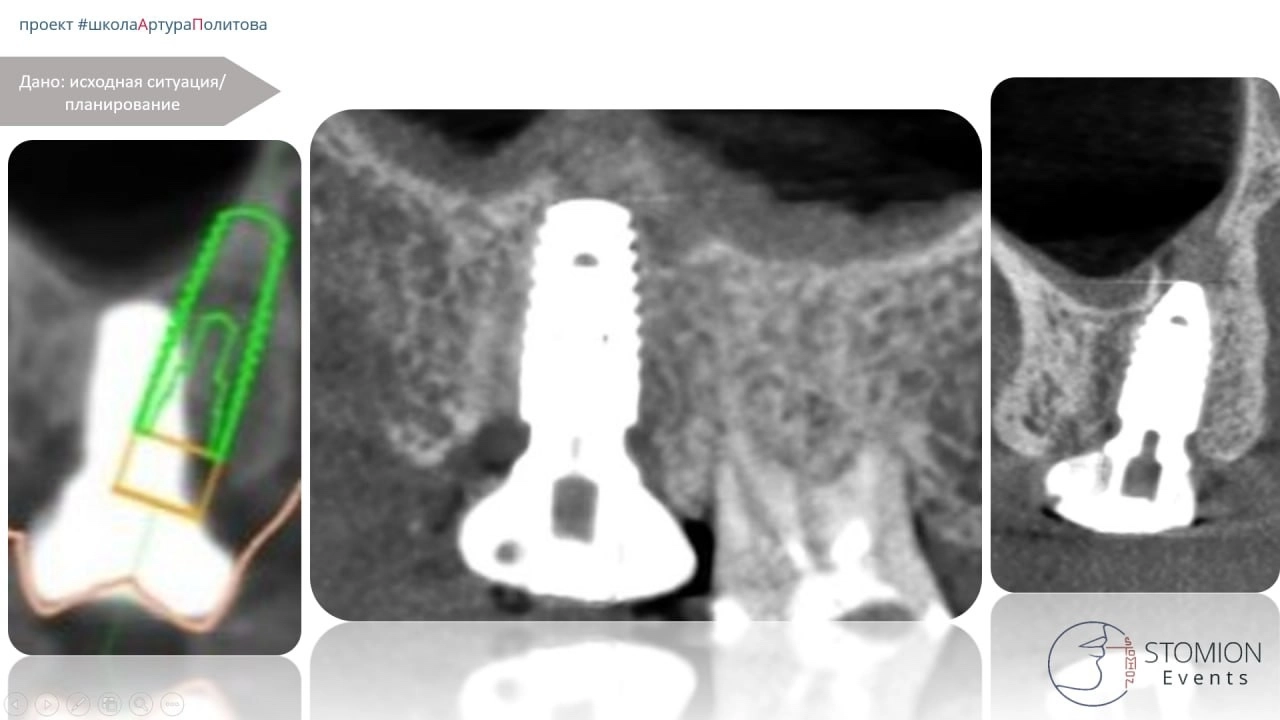

План лечения (этап 1)

• Удаление фрагментов имплантата.

• Активный кюретаж дефекта.

• Одномоментная установка имплантата MiS C1.

• Заполнение дефекта аутотрансплантатом из бугра верхней челюсти.

• Применение ИФДМ